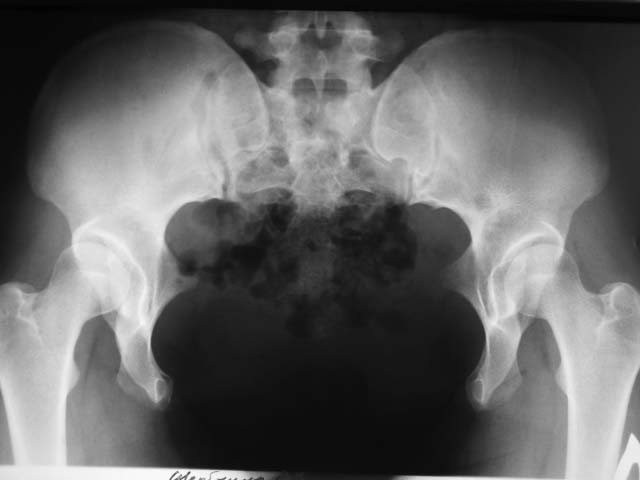

Врожденная деформация таза

Пациентке 23 года. Деформация врожденная. Беспокоят умеренные боли в задних отделах таза после длительной ходьбы.

Ходит - не хромает. Деформация стабильная. Что делать? И делать ли...

Боли после длительной ходьбы при таком расхождении абсолютно нормальное явление. Со временем, вероятнее всего придется вмешаться, тем более если предполагается беременность. ИМХО аппарат и пластина на переднее полукольцо будут состоятельны при остеотомии крестца.

В литературе описание врожденннего диастаза симфиза упоминается в разделе малформации передней стенки живота с грыжей уро-генитальных органов. Лечение экстропии или гипоспадии в ранней стадии описано во множественных публикациях, и только Vaz C, Salvador MJ, Malcata А "Congenital diastasis of pubic symphysis" описывает диастаз без вовлечения внутренних органов.

Литературный поиск по поводу лечения у взрослых результатов не дает, и, возможно, лечение зависит от вовлечения в процесс внутренних органов, и поэтому

вряд ли в данном случае совместима тактика лечения (наружными фиксаторами) постпартум или постравмтатического разрыва симфиза.